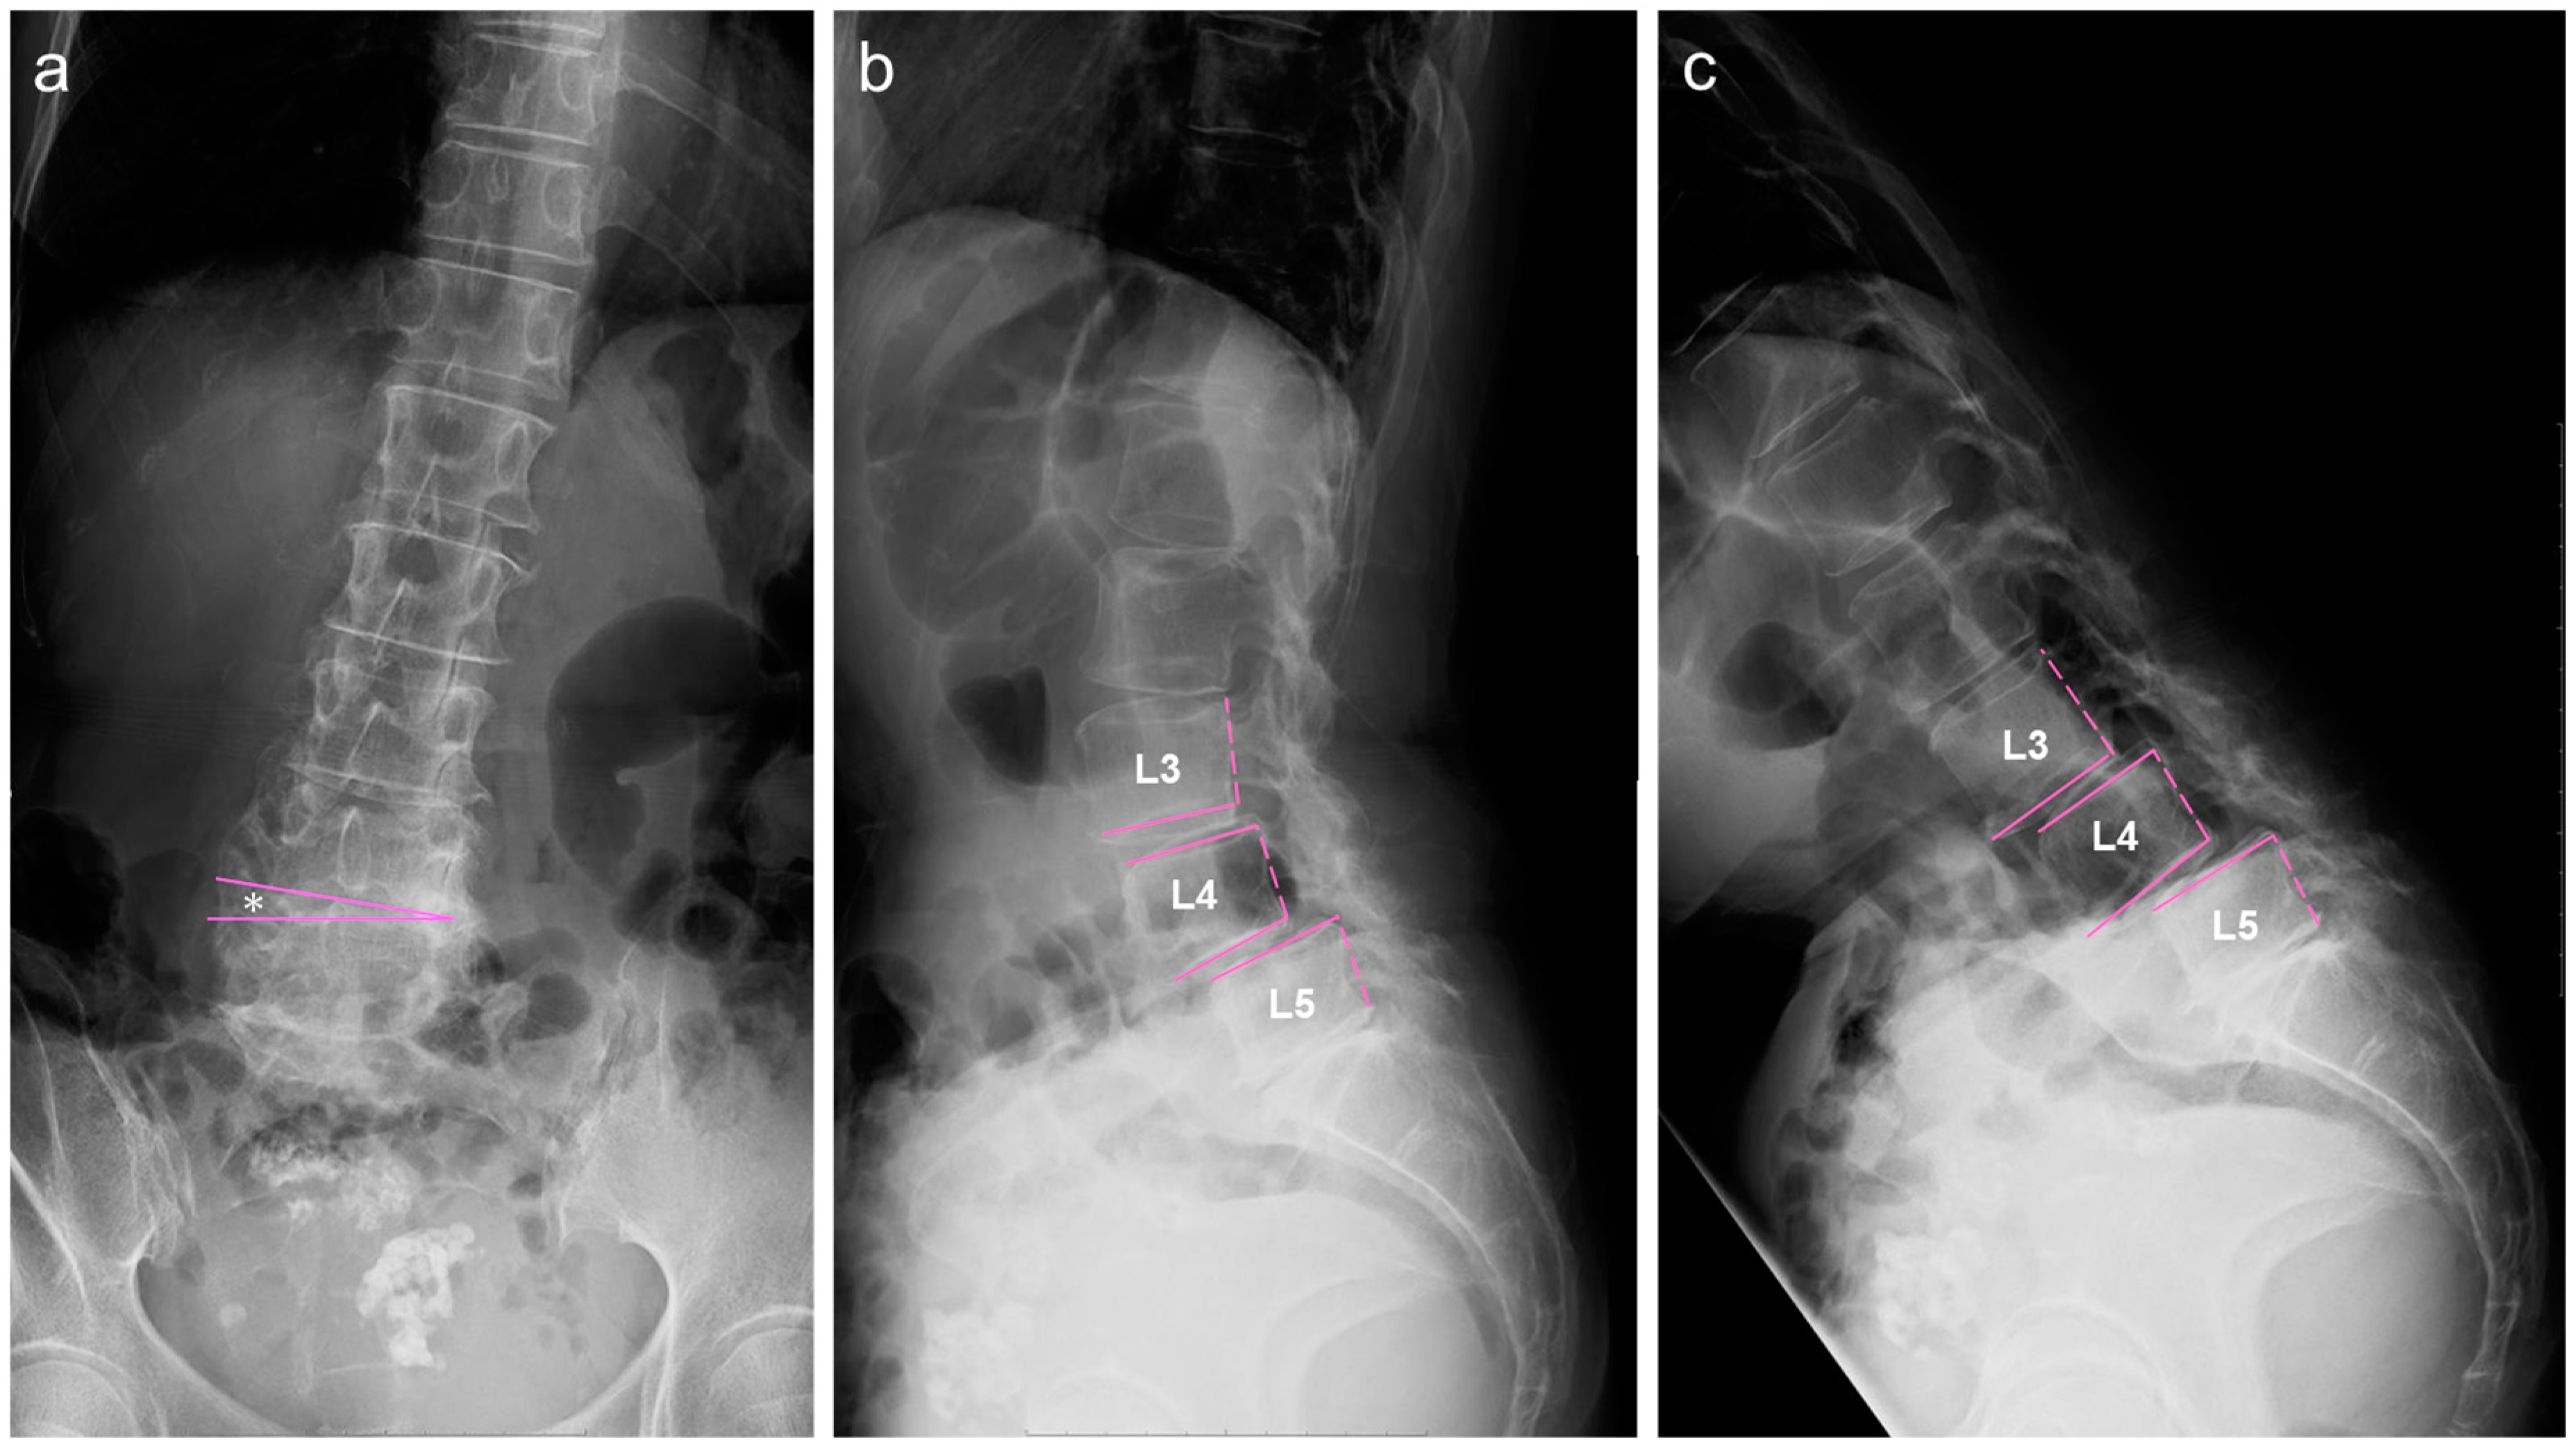

2.2. Image Examinations at First Visit